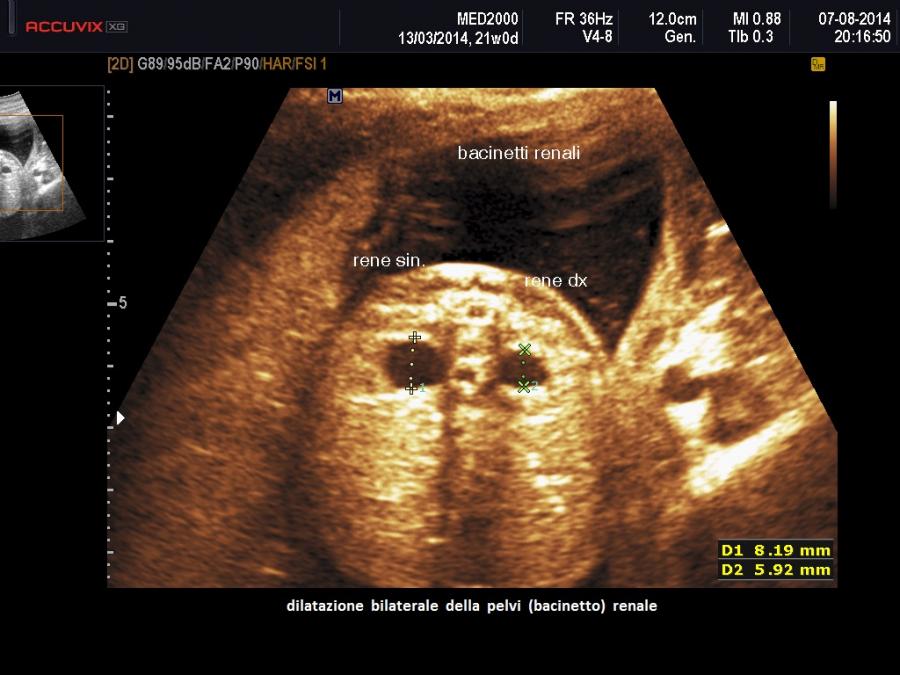

• pielectasia e calicectasia: consiste nella dilatazione della pelvi o bacinetto e dei calici; la diagnosi di pielectasia è effettuata allorquando il diametro antero-posteriore della pelvi è superiore ai 7 mm. Nelle forme severe di pielo-calicectasia si ha compressione del parenchima renale con successiva corticalizzazione.